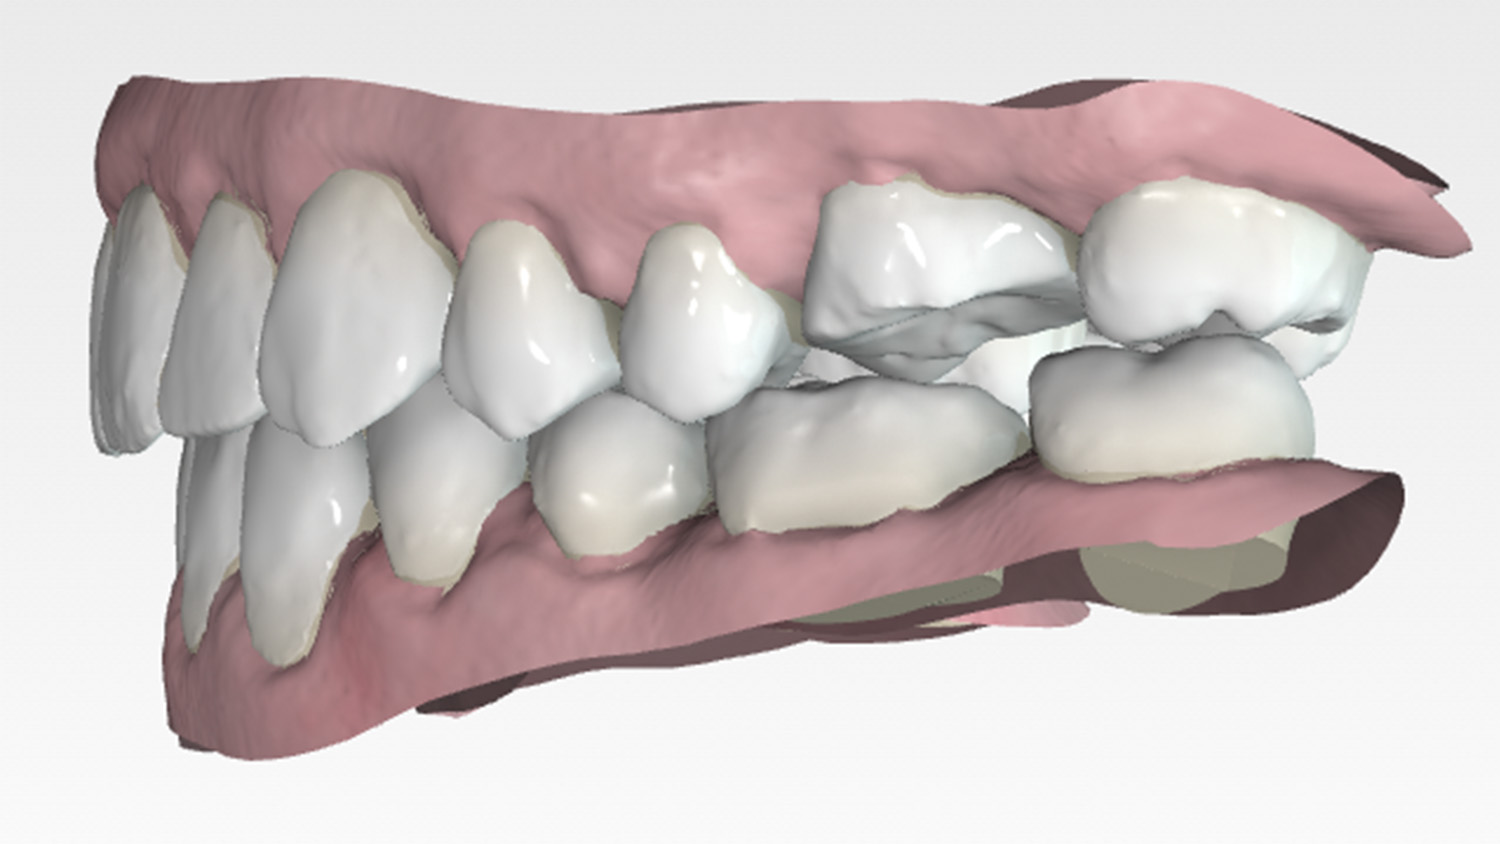

Intraoral examination showed an Angle Class III relationship on both sides, along with an anterior open bite. Additionally, a narrow maxilla with a bilateral posterior crossbite was observed.

The primary goal of the treatment was to correct the transverse deficiency of the maxillary arch (>5 mm) and resolve the skeletal crossbite. MARPE was used to address this transverse issue.

Once the transverse discrepancy was corrected, treatment continued with Spark Aligners to address the vertical plane. The planned vertical correction involved extruding the upper anterior teeth, with 1.7 mm of extrusion in the upper arch, and 1.5 mm in the lower arch using attachments. To assist in bite closure, turbo bites were employed to intrude the mandibular molars.

As shown in the accompanying images, the planned vertical correction was fully achieved. At this stage, provisional composite veneers were placed from canine to canine in the upper arch to enhance the patient’s aesthetics and compensate for Bolton’s discrepancy.